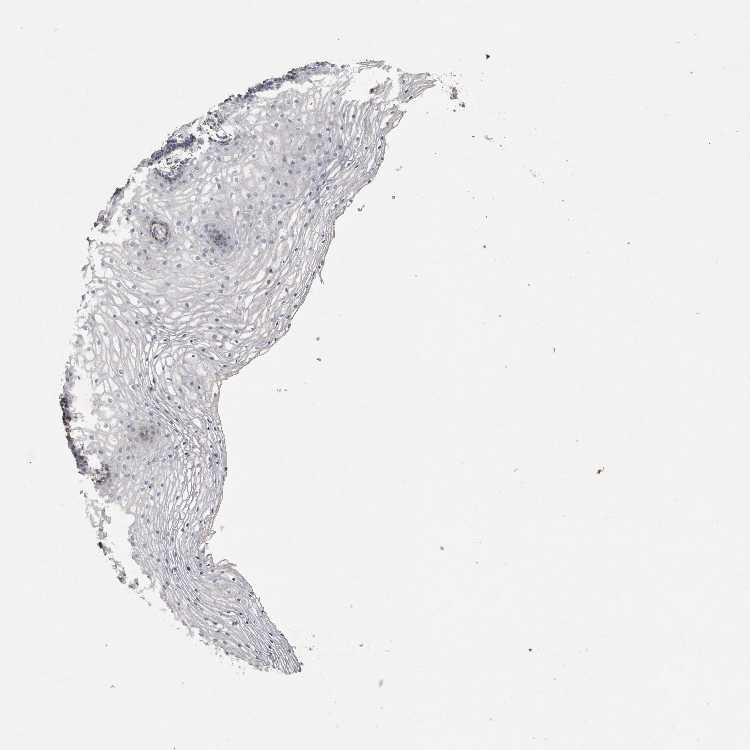

TISSUE PRIMARY DATA VAGINA Show tissue menu

VAGINA - Antibody stainingi

Antibody staining in the annotated cell types in the current human tissue is reported as not detected, low, medium, or high, based on conventional immunohistochemistry profiling in selected tissues. This score is based on the combination of the staining intensity and fraction of stained cells.

Each image is clickable and will lead to virtual microscopy that enables deeper exploration of all samples and also displays staining intensity scores, fraction scores and subcellular localization as well as patient and tissue information for each sample.

Antibody HPA011868Antibody CAB024949

Squamous epithelial cells MediumNot detected